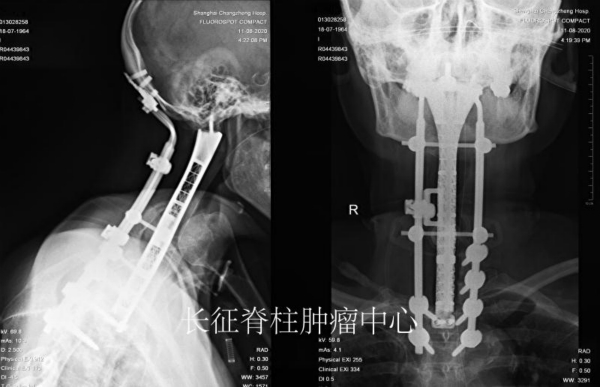

图说:全球最长节段颈胸段脊柱肿瘤切除术   来源:长征脊柱肿瘤中心(下同)

新民晚报讯(记者 郜阳 通讯员 王根华)超长枕颈胸段切除重建一直是医学界悬而未决的世界难题。近日,海军军医大学第二附属医院(上海长征医院)脊柱肿瘤中心肖建如教授团队为罹患颈胸椎巨大恶性脊索瘤的何女士成功实施了世界首例从颅底横跨颈椎,直通胸2椎体8椎节切除术,并为她安装3D打印人工寰枢胸椎复合假体及重建术,攻克了超长枕颈胸段切除与重建这一难关。这是迄今全球最长节段颈胸段脊柱肿瘤切除术,也是自主研发最长跨度的3D打印人工寰枢胸椎复合假体。

随后,根据患者的影像组学数据,团队自行设计出与患者全颈椎和胸椎的形态和长度相仿的3D打印“寰枢胸椎复合钛合金假体”,并通过动态力学模拟测试,运用于前方颅颈胸重建。接着,肖建如、矫健实施了二期前路颈胸椎肿瘤切除重建内固定术。经过4小时奋战,手术团队在3D鹰眼可视化高倍显微镜下彻底切除了寰枢椎至胸1椎体脊索瘤后,将定制的复合假体精准固定于患者颅底双侧枕骨髁和胸2椎体,并巧妙实现了前方复合假体与后路固定棒的前后链接。术后经呼吸科协助脱机训练,患者呼吸及脊髓神经功能逐渐改善,近期将转至康复医院继续治疗。